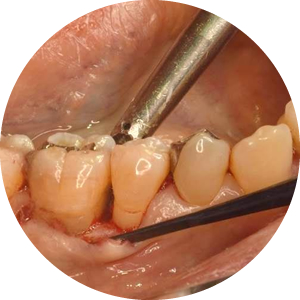

歯周基本治療

歯周基本治療には、スケーリング、ルートプレーニング、歯磨き指導があります。

- スケーリング

- 歯茎のラインよりも表に出ている歯石を、機械で弾き飛ばすように取り除いていきます。

- ルートプレーニング

- 歯周ポケット内部にこびりついた歯石を、器具を用いて丁寧に取り除き、歯根の表面を滑らかに仕上げます。

歯周外科処置

深い歯周ポケットが残っていると歯周病が進行しやすいため、歯周外科処置で歯周ポケットを浅くする手術をおすすめすることもあります。